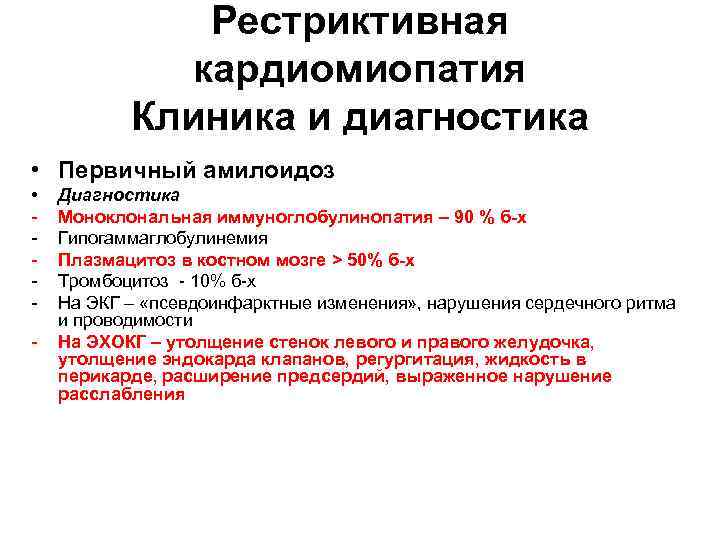

Рестриктивная кардиомиопатия Клиника и диагностика • Первичный амилоидоз • - Диагностика Моноклональная иммуноглобулинопатия – 90 % б-х Гипогаммаглобулинемия Плазмацитоз в костном мозге > 50% б-х Тромбоцитоз - 10% б-х На ЭКГ – «псевдоинфарктные изменения» , нарушения сердечного ритма и проводимости На ЭХОКГ – утолщение стенок левого и правого желудочка, утолщение эндокарда клапанов, регургитация, жидкость в перикарде, расширение предсердий, выраженное нарушение расслабления

Рестриктивная кардиомиопатия Клиника и диагностика • Первичный амилоидоз • - Диагностика Моноклональная иммуноглобулинопатия – 90 % б-х Гипогаммаглобулинемия Плазмацитоз в костном мозге > 50% б-х Тромбоцитоз - 10% б-х На ЭКГ – «псевдоинфарктные изменения» , нарушения сердечного ритма и проводимости На ЭХОКГ – утолщение стенок левого и правого желудочка, утолщение эндокарда клапанов, регургитация, жидкость в перикарде, расширение предсердий, выраженное нарушение расслабления